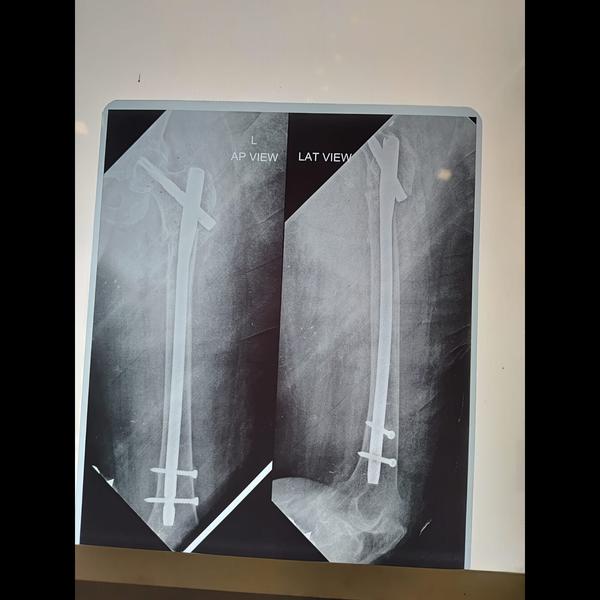

Subtrochanteric femur fracture fixation done 3 months post op x ray !